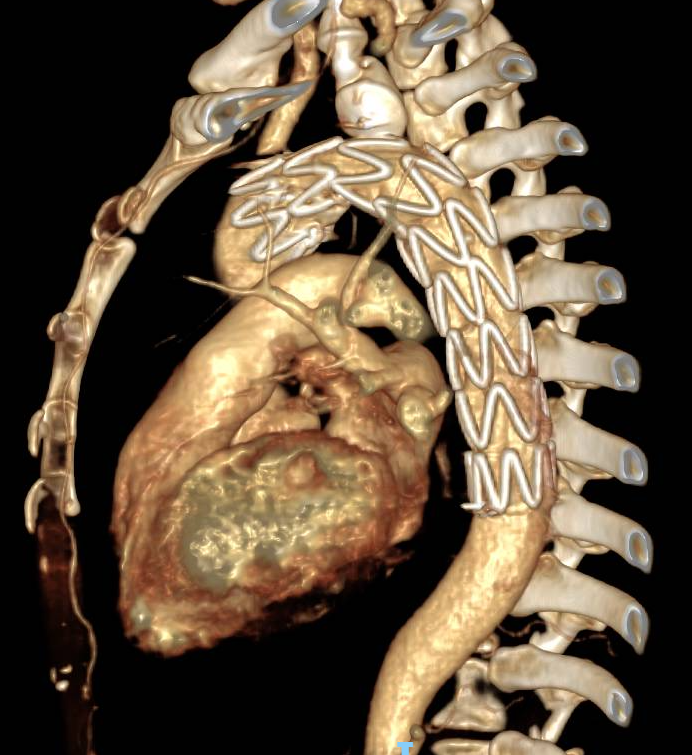

经过周密计划,该科室制定了分阶段杂交手术方案:心血管外科先通过2处5cm的手术切口行颈动脉—锁骨下动脉搭桥,建立血流通路;接着介入科团队接力,通过3处不超过1cm的微创伤口完成胸主动脉夹层腔内覆膜支架隔绝术,并用血管塞精准封堵左锁骨下动脉起始段以避免术后支架内漏。

△注:支架精准定位,稳定释放,成功以“人工血管”将主动脉破口隔绝。

整台手术历时7小时50分钟,术程中患者生命体征保持平稳,总出血量控制在50ml以内。这种复杂且高危的四级手术,单靠任何一个学科都难以完美完成。正是MDT团队的精诚合作,让患者在最小的创伤下获得了最有效的治疗。